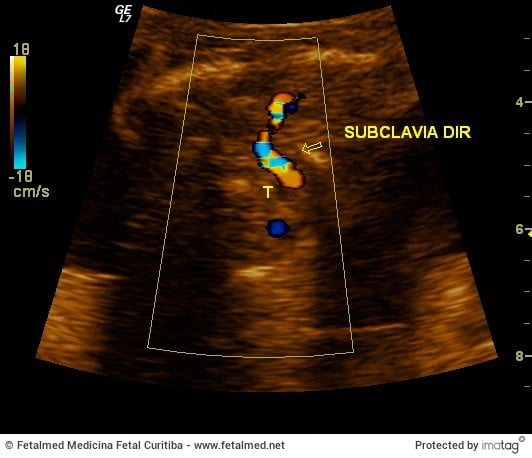

Artéria Subclávia Direita Aberrante (ARSA)

A artéria subclávia direita normalmente tem origem como primeiro vaso do tronco braquiocefálico no arco aórtico. Uma artéria…